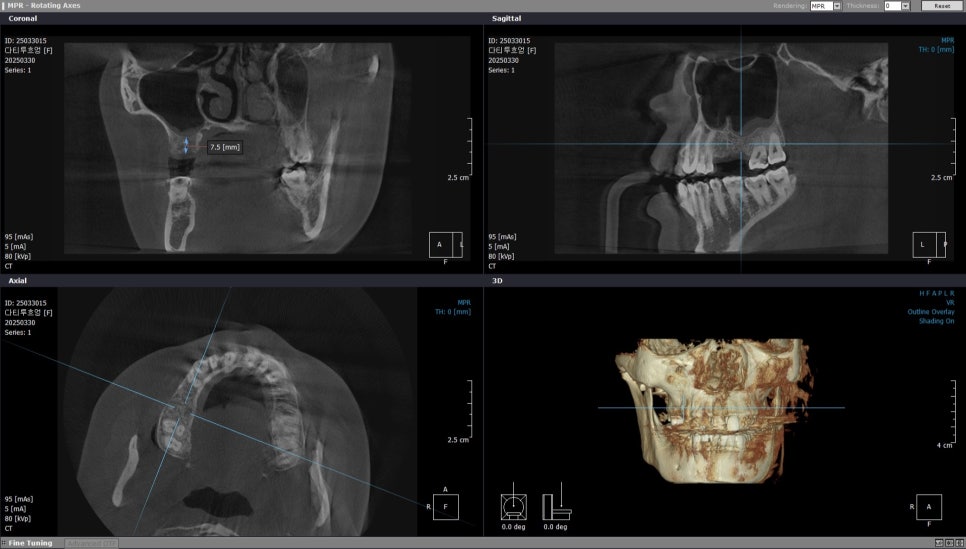

특히 오른쪽 위 첫번째 어금니 같은 경우

잔존골 높이가 약 7.5mm로 측정되어

상악동 거상술 없이는 힘든 케이스였는데요.

오른쪽 위 첫번째 큰 어금니 부위 CT

검사 결과를 정리해보면

오른쪽 위 두번째 작은 어금니는

골높이가 11.4mm로

임플란트 식립에 충분합니다.

오른쪽 위 두번째 작은어금니 부위

오른쪽 위 첫번째 큰 어금니의 경우

잔존골이 약 7.5mm 밖에 되지 않아

상악동 거상술이 필수입니다.